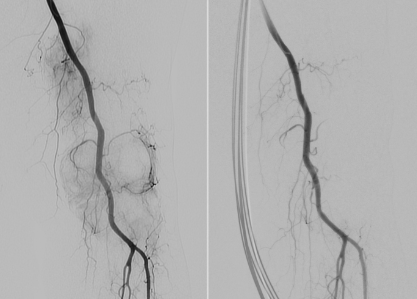

Wenn konservative Therapien bei chronischen Gelenkschmerzen nicht mehr wirken und ein operativer Eingriff (noch) nicht infrage kommt, bietet die moderne Medizin mit der Transarteriellen Periartikulären Embolisation (TAPE) eine innovative, minimalinvasive Lösung. Bei anhaltenden Gelenkschmerzen - etwa infolge von Arthrose oder Sehnenentzündungen - entstehen oft winzige, krankhafte Blutgefäße (Neovaskularisationen), die eine zentrale Rolle bei Entzündung und Schmerzentstehung spielen. Hier setzt TAPE an: Über einen feinen Katheter, meist durch die Leistenarterie, werden diese schmerzverursachenden Gefäße im Gelenk gezielt verschlossen, während die gesunde Blutversorgung erhalten bleibt. Die Folge: Entzündungen gehen zurück und der Schmerz lässt nach. Für die Patient*innen bedeutet das einen schonenden Eingriff in Lokalanästhesie von meist nur rund einer Stunde Dauer. In der Regel können sie bereits am nächsten Tag wieder nach Hause gehen.